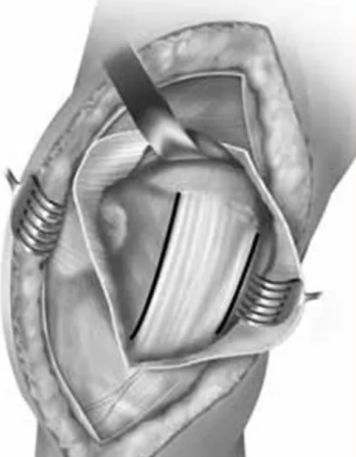

在胫骨结节外侧沿髌骨外侧缘行皮肤切口,延伸至髌骨的外上角,切口长度约12-15cm。

锐性分离膝关节部位皮瓣直至暴露外侧髌韧带,沿髌韧带作梯形手术切口,暴露膝关节,如图1,该切口远端起始于髌腱胫骨止点外侧,沿髌骨边缘的髌韧带延伸至股外侧肌肌腹。

后按一下四个步骤进行股骨远端暴露:1. 使用手指将髌腱从髌后脂肪垫上钝性分离;2. 完全切除髌后脂肪囊和滑囊至半月板韧带水平,注意此时需保护半月板和半月板间韧带;3. 完全松解髌韧带远方胫骨结节止点;4. 最后松解髌韧带上方以获得进入髌上囊的空间。

在胫骨近端靠近内侧半月板水平放置霍夫曼拉钩以牵开髌骨,在髌上囊水平放置另一个霍夫曼拉钩牵开近段股中间肌完成微创swashbuckler入路。

沿髌韧带所作的梯形手术切口,注意该梯形手术切口仍位于髌韧带内而未延伸至股外侧肌腹

微创swashbuckler入路与股骨轴线呈30度角所拍摄的图片。图中整个股骨远端关节面得到接近完整的暴露